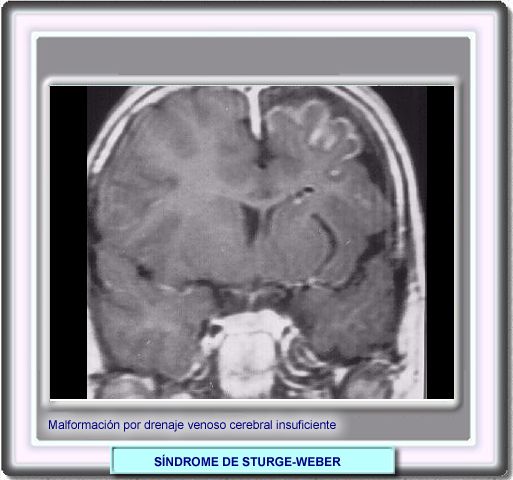

SÍNDROME DE STURGE-WEBER

En el síndrome de Sturge-Weber, ipsilateralmente al nevo facial, se observa una circulación anormal de la sangre que ocasiona:

• disfunción cerebral

• inestabilidad eléctrica (convulsiones)

• atrofia cortical

Por regla general, los lóbulos occipitales son los primeros en ser afectados, pero también pueden verse afectados los lóbulos temporal y parietal y, más raramente, el lóbulo frontal